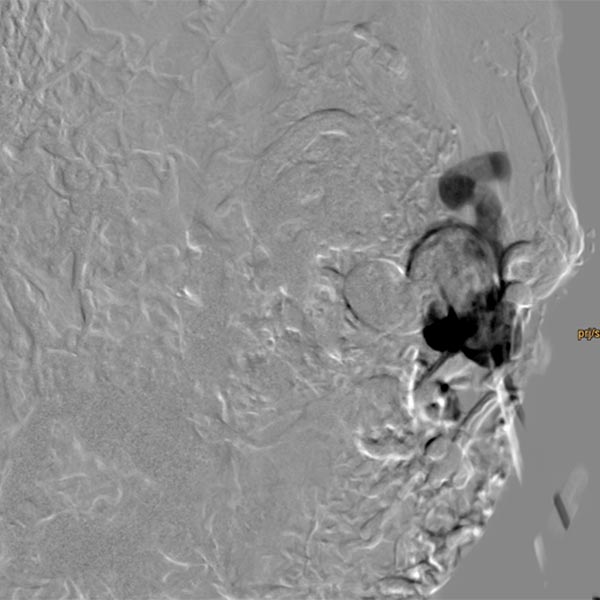

Direkte perkutane Punktion des Nidus mit einer Nadel und Durchführung einer DSA. Damit Kontrolle der korrekten Lage der Nadelspitze vor Embolisation mittels Ethylen-Vinyl Alkohol-Kopolymer in Direktpunktionstechnik.

Erneute Direktpunktion des Nidus und DSA zur Überprüfung der Nadellage.

Langsames, direktes Auffüllen des Nidus und der abführenden Venen mittels Ethylen-Vinyl Alkohol-Kopolymer (EVOH) in Roadmap-Technik. Bereits vorinjeziertes EVOH wird in dieser Technik wegsubtrahiert und ist nur in Umrissen erkennbar.